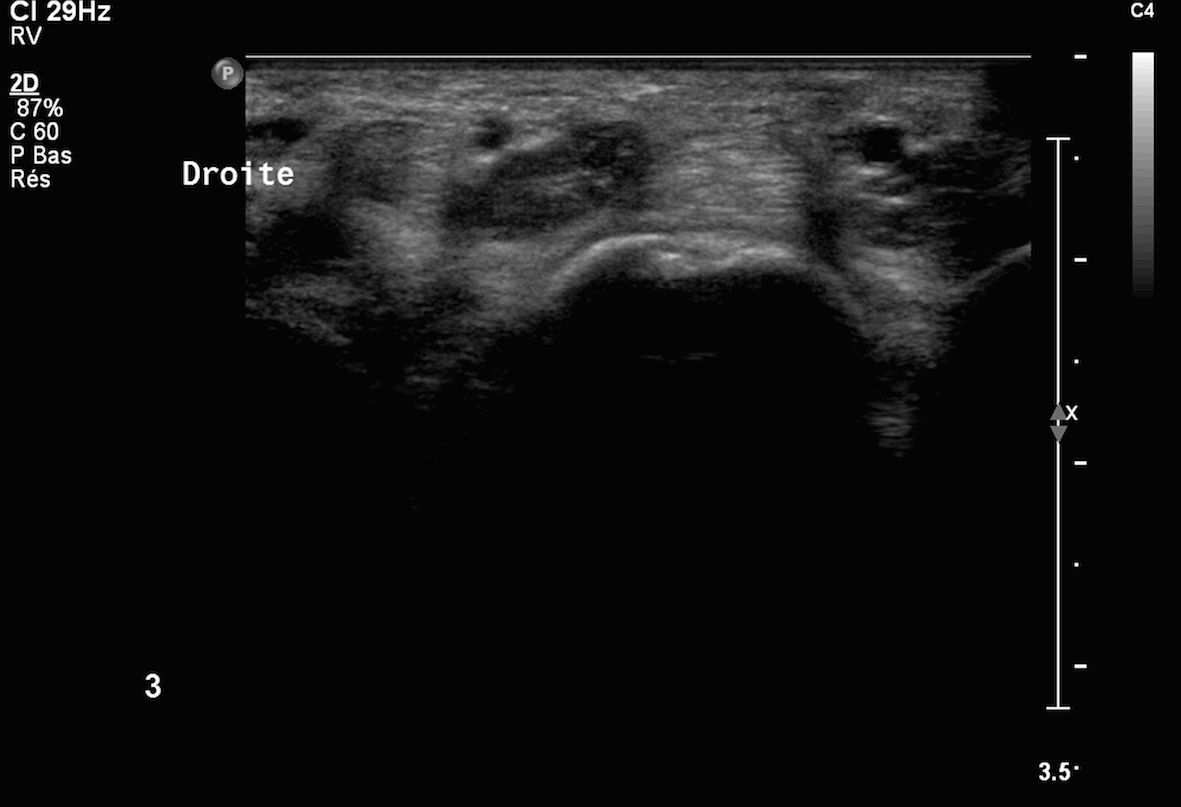

4Infiltration du tendon du tendon 3ième fléchisseur de la main (images 1 et 2) sous contrôle échographique

Images 3 et 4 visibilité du produit anti inflammatoire injecté sous deux incidences orthogonales en regard de la gaine péri tendineuse